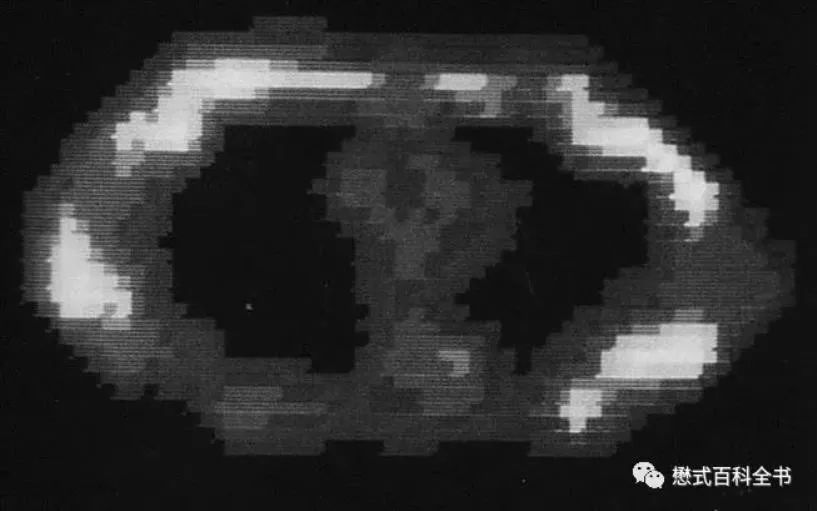

在美国,纽约大学的雷蒙德·达马迪安教授团队则在医学成像方面,拔得头筹,他们研制的医用核磁共振设备(图7)于1977年7月3日到了第一幅人体磁共振图像——胸部轴位质子密度加权图像(图8),标志着MRI技术在医学领域应用的开始,因此7月3日也被学界认为是医学磁共振成像技术的“生日”。

图8 第一幅人体磁共振图像